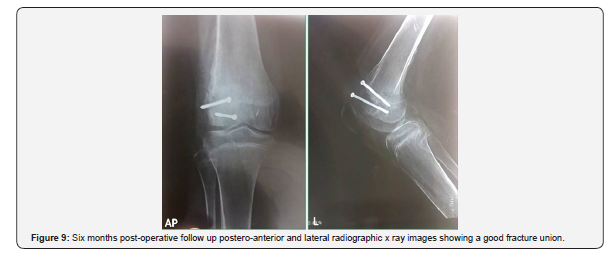

According to our knowledge seven cases were reported in the literatures discussing Hoffa fractures in skeletally immature patients until last search at 30 august 2019 ( Table 1)[4-10] . Five of these seven cases were fresh fractures and early managed operatively with different approaches and different techniques and the result were satisfactory [4-8]. However, only two cases were described in the literatures as a missed Hoffa fracture in an eight year old girl and twelve year old boy went to a nonunion which managed operatively and fixed with cannulated screws and the result were satisfactory in the 1st case the child has virtually full range of motion of the knee and no evidence of growth disturbance, also in the second case radiographic union was observed after 3 months, and after 2 years of follow-up, the child had excellent functional outcome [9,10]. In this study we report another case of missed non-united lateral condyle Hoffa fracture in a twelve-year-old boy with a clear picture of pseudoarthrosis. Moreover, vigorous antero-posterior instability was observed during clinical examination, in spite of normal cruciate ligaments and other intraarticular structures in MRI examination .We referred this instability to the fracture geometry which is type I Hoffa fracture that extend from an extra-articular location at the junction of the posterior femoral shaft and the proximal aspect of the femoral condyle to the posterior aspect of the condylar articular surface. And the anterior cruciate ligament (ACL) insertion in addition to the popliteus tendon, and the lateral head of the gastrocnemius origin remain attached to the unstable non-united condylar fragment (figure 4).